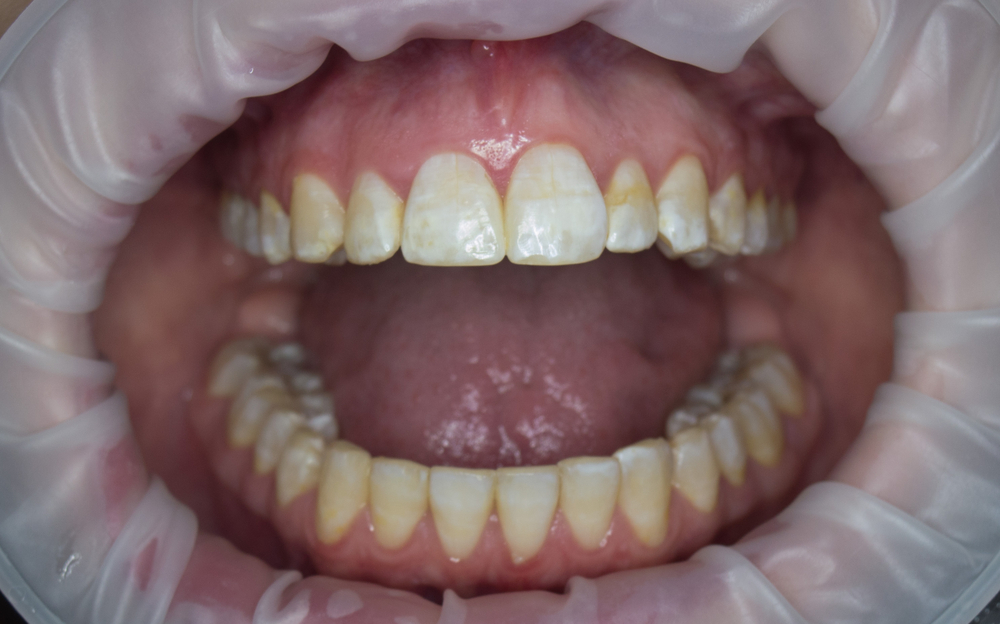

Флюороз обладает специфическими симптомами. При эндемической форме заболевания на поверхности зубных единиц появляются белые полосы или пятна. В течение нескольких лет они меняют окраску, становясь желтыми и бурыми. Очаги патологии формируются на резцах верхней челюсти. Накопление в организме пациента значительных объемов фтора приводит к поражениям других зубов, появлению на эмали многочисленных сколов и очагов эрозии.

Многочисленные мелкие точки белесой окраски на внешних поверхностях резцов, клыков или премоляров характерны для пятнистой формы заболевания. Пятна обладают блестящей гладкой поверхностью, плавно переходящей в здоровую зубную эмаль.

Меловидно-крапчатый флюороз проявляется в виде матовых очагов пигментации на поверхности зубов. Пятна окрашены в желтый цвет, внутри них присутствуют мелкие участки деструкции. Зубная эмаль склонна к быстрому разрушению — сквозь истонченную поверхность можно разглядеть темно-коричневый дентин.